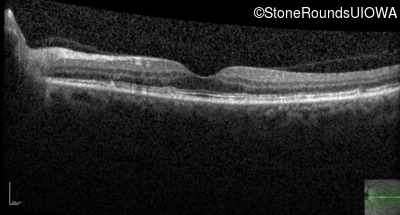

Optical Coherence Tomography - Right - 20/25 +2

Exemplar / OCT Stack

OCT Stack